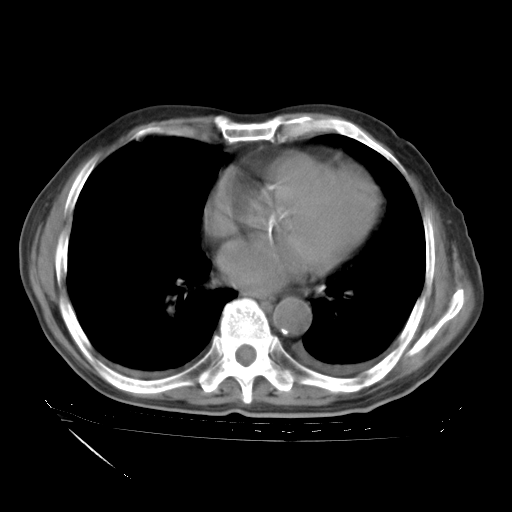

甲强龙80mg/日+抗结核治疗(异烟肼+利福霉素+乙胺丁醇)10天。复查肺部CT。

治疗10天肺部CT

补充下:5月9日胸部CT:似乎已见双下肺胸腔积液了,鉴于目前有下肢水肿,肝功示:白蛋白低,应注意多浆膜腔积液(漏出液可能大?),需注意!